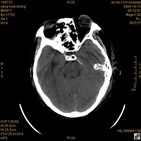

病人杨XX,男,青云街道办事处路踏泉村,住院号51666,CT号:104770。病人因“高血压脑出血”在新泰市人民医院住院治疗5天,治疗效果不佳转入我院,复查CT示左基底节血肿,病人昏迷状态,给予血肿清除术,术后2天复查CT,血肿完全清除,病人恢复好,治疗效果满意。附病人术前术后CT片资料如下。

术后46小时复查CT

术后46小时复查1 术后46小时复查2 术后46小时复查3 术后46小时复查4